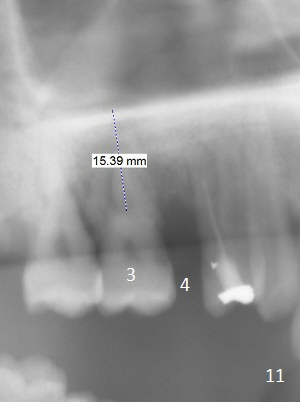

A 36-year-old man (ex-smoker) has advanced chronic periodontitis (Fig.1-5). His chief complaint is "I cannot chew on the right side now because of pain (Fig.1: #3 abscess <) and the bottom front teeth are loose (Fig.2,5: #23-26)". He has not masticated on the left side because of the mobile teeth. Due to finance, implants will be placed at #3,4 (Fig.12), 23 and 26 at the appointments of scaling & root planing.

Class II Division II malocclusion (Fig.2,6) will make it difficult to restore #23-26 implant-supported FPD. Although the teeth #7-10 may need to be replaced later (Fig.7,8), enameloplasty will be conducted for #7-10 (Fig.9 white area; Fig.12 black circles (gross reduction)) prior to #23-26 extraction and implant placement (Fig.10). To be flexible in restoration (angulation) and possible future hybrid denture, 2-piece narrow implants will be placed (3.0 or 3.3 mm) instead of 1-piece ones. In fact CBCT shows that the narrowest regular implant (3.8 mm) can be placed in the lower anterior region (Fig.13-15).